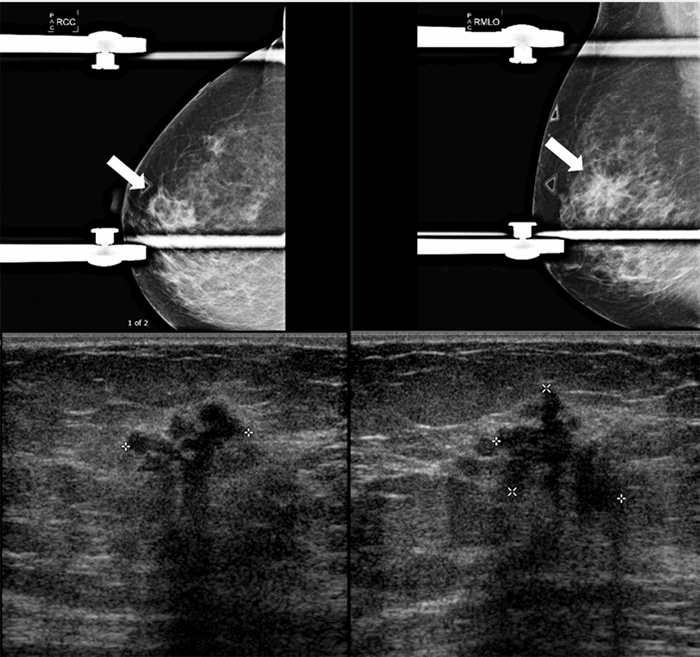

A 59-year-old female presented initially with vague symptomatology of hyperparathyroidism. She had a history of type 2 diabetes and hypothyroidism, and her medical workup confirmed a biochemical diagnosis of mild primary hyperparathyroidism. She was referred for surgical evaluation. Localization studies to identify her hyperfunctioning parathyroid included neck ultrasound and sestamibi scan with SPECT CT. Ultrasound imaging was nonlocalizing for a parathyroid lesion; however, sestamibi scan revealed suspicious tracer uptake in the right breast (Figure 1).

Figure 1.Sestamibi scan: Sestamibi imaging demonstrating uptake in the right breast.

After concluding the unknown mass was not due to a possible artifact such as clothing, physical exam was performed to determine if there were any palpable findings in the area of increased uptake. A thickened area approximately 2 cm was palpated on the right breast. The patient was referred to the breast oncology department for further workup. Her last mammogram had been exactly 12 months prior to her referral to breast oncology. Right diagnostic mammogram and ultrasound confirmed the presence of a hypoechoic mass measuring 20 x 16 x 18 mm (Figure 2).

Figure 2. Diagnostic imaging of the breast: Diagnostic mammogram and ultrasound images of the palpable area identified on sestamibi imaging.